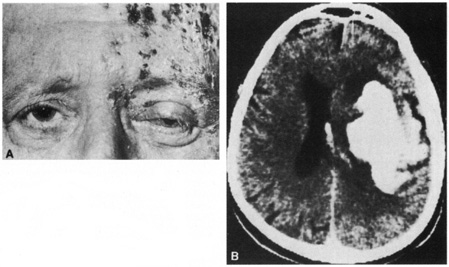

Herpes zoster ophthalmicus behaves like zoster infections elsewhere in the body. The incidence increases with age. Pain, often severe, may precede, be concurrent with, or follow the vesicular skin eruption. Occasionally no skin lesions occur; this is referred to as zoster sine herpete. The vesicular eruption usually involves only one dermatome, but severe systemic eruptions can occur (the latter appear most often in immunocompromised persons or in persons with malignancy). Fever, malaise, headache, and lymphadenopathy may be present at the onset. Fifty percent of cases have ocular involvement, which can be predicted if vesicles appear on the lid margin or if Hutchinson's sign is present.39,40 In 1886, Hutchinson noted that when the nasociliary branch to the tip of the nose is affected, intraocular involvement is likely. Ocular changes include conjunctivitis, episcleritis, scleritis, keratitis, iritis, chorioretinitis, optic neuropathy, glaucoma, ocular motor palsies, and Horner's syndrome.39,41,42 On rare occasions, a contralateral hemiplegia may occur (Fig. 7).39,43–45 A virus-induced angiitis of cerebral vessels has been shown by angiography and pathology in several cases. Although patients with neoplastic or other debilitating diseases are predisposed to the development of herpes zoster infections, a neoplasm is discovered in less than 1% of otherwise healthy persons with cutaneous zoster.

Fig. 7. A: A 70-year-old man with herpes zoster ophthalmicus and a left-cerebral infarction. B: Computed tomography demonstrates a hemorrhagic infarction.